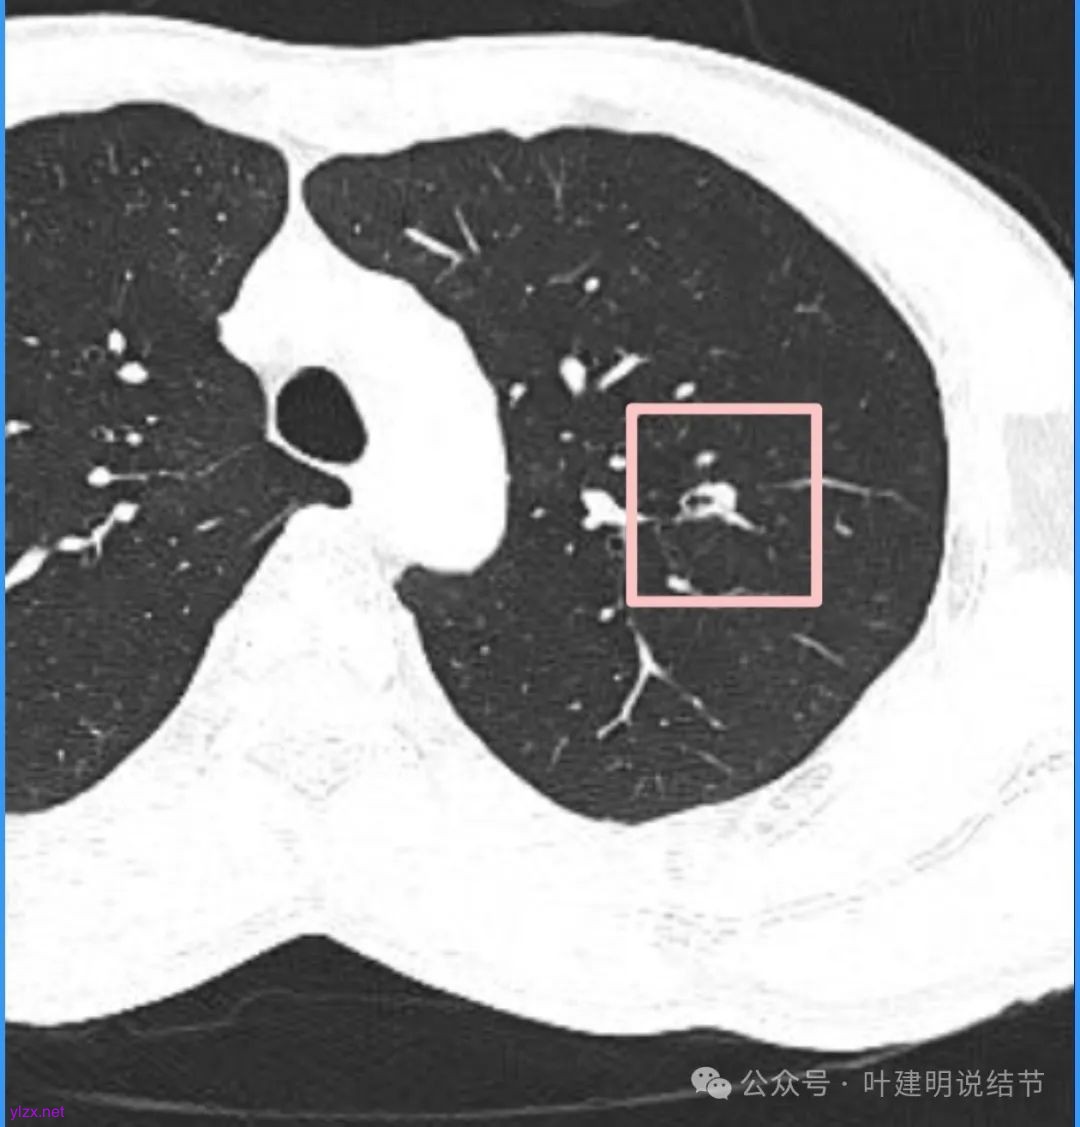

再看看近半年前2024年11月时的影像:

我们发现一是病灶与25年3月的几乎没有区别,二是原来蓝色箭头处不太像血管,而是结节边缘的一部分,而结节灶内又是有扩张支气管的。

左肺上叶这个病灶总体上来讲2025年3月的与2024年11月份相比没有显著进展。我们逐层从细节上去分析,会发现:1、病灶开始出现的层面就有临近的支气管扭曲变形,这些人用肿瘤导致的牵拉不能解释,反而用细支气管扩张伴慢性炎容易解释;2、病灶内部仍然多个层面都有见到扩张的细支气管,可是如果是肿瘤,与导致细支气管扩张相应的病灶本身的收缩力或者边缘毛刺又不明显;3、病灶边缘基本上都比较光滑平直,没有像外周浸润性生长的枫叶或者毛刺;4、虽然有血管贴边或者进入,但是说不上显著的血管异常增粗;5、整体来讲病灶实性成分密度过高,随访对比进展不明显,用结节是恶性不太能够解释相应的影像表现,所以我倾向于考虑是细支气管扩张伴有周围慢性炎或者肉芽肿性炎。至少从风险高低的角度来看,几个月的间隔没有明显进展的情况下加上位置又不好,如果手术需要切除范围比较多,所以应该在随访观察比较稳妥,可以考虑半年复查对比。意见供参考!